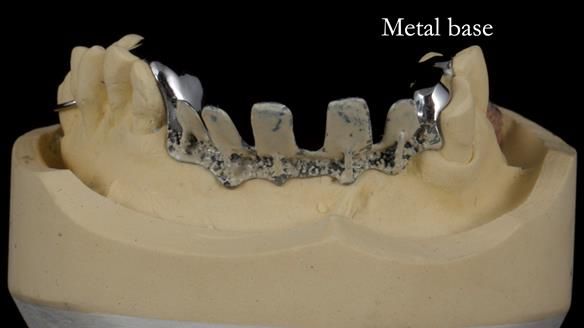

Keith’s case was one of the most challenging and rewarding cases I’ve treated this year. This 64 year old man presented with ill-fitting acrylic partial dentures that lacked stability, retention, and aesthetics. They constantly broke. He had lost the upper front teeth in a road traffic accident in his early 20s. The unopposed teeth had erupted, taking up space. After careful planning, we made a durable, metal-based upper partial denture/splint to address his dental concerns. He loved the outcome.

1. Denture design: A custom cobalt-chromium framework was Scandinavian-designed to maximise stability, protect the remaining teeth, and allow for future additions if needed.

Keith’s denture incorporated a Duracetal shell clasp on upper right first premolar (Myerson), which are designed to be virtually visible, providing a more aesthetic solution while enhancing patient comfort. The Scandinavian-inspired approach, based in modern removable prosthodontic techniques, ensured the denture was not only durable but also visually pleasing. Additionally, the design was carefully planned to allow for future modifications, ensuring that if Keith loses additional teeth, the denture can be adapted rather than replaced entirely.